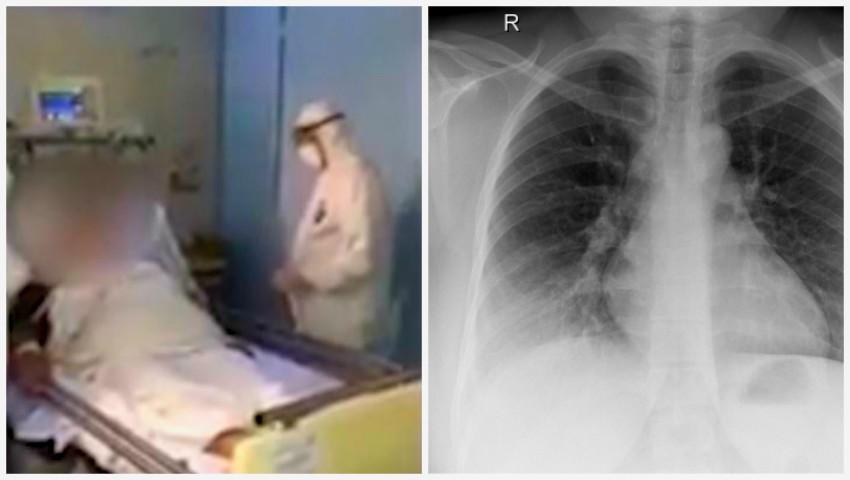

"Pacienta se află la terapie intensivă în boxă izolată. Uşor pozitivă. Radiologic, semnele de inflamaţie au cedat din ambele părţi. Parametrii biochimici s-au îmbunătăţit. Suntem optimişti şi sperăm la un final pozitiv. În principiu, dinamica este sub control şi este normal", a spus Anatol Cibotaru, potrivit publika.md.Potrivit lui, pacienta se află izolată, într-o boxă, în secţia terapie intensivă, unde ventilaţia este separată."Pacienta a fost transportată cu AVIASAN, a fost adusă la spital, unde a fost întâmpinatp de către doi reanimatologi, un epidemilog. A fost transportată prin liftul nr. 12. Ulterior, liftul a fost prelucrat, traseul a fost prelucrat pe parcursul a două ore. Acces la ea au doar două asistente medicale şi un medic", a mai spus Cibotaru.Potrivit, informațiilor prezentate de Ministerul Sănătăţii, Munici şi Protecţiei Sociale, pacienta a fost internată în Italia, pe 4 martie curent, cu diagnoza de bronhopneumonie bilaterală, febră și tuse. I s-a prescris tratament cu antibiotice la domiciliu și a fost plasată în carantină la domiciliu până la confirmarea infecției prin Coronavirus de tip nou. Însă aceasta a decis să revină în Republica Moldova.Pacienta a fost preluată de echipa Serviciului 112 din aeronavă și internată în stare gravă în cadrul instituției spitalicești. Testul realizat în cadrul laboratorului Agenției Naționale pentru Sănătate Publică a confirmat prezența Coronavirusului de tip nou. Totodată, doamna suferă de mai multe boli cronice: diabet zaharat, hipertensiune arterială, supraponderabilitate de gradul 2. La moment, starea pacientei este gravă, dar stabilă.